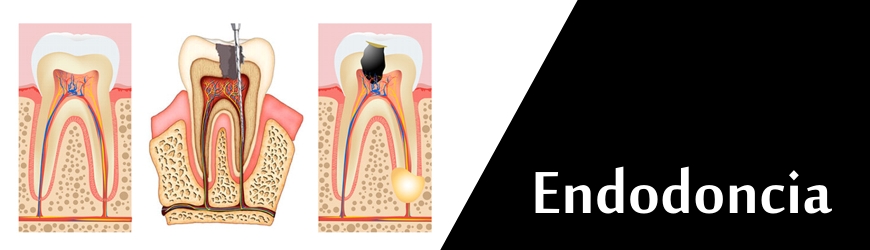

ENDODONCIA

Consiste en desvitalizar una pieza dental.

Para ello disponemos de la tecnología más

avanzada de instrumental rotatorio y

radiografía digital.